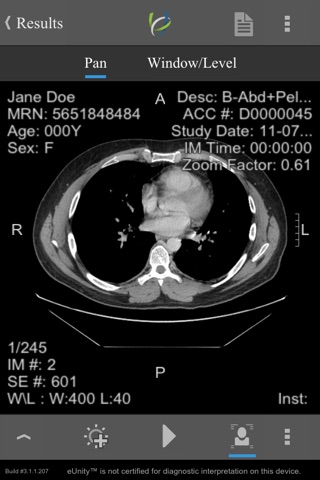

Simple, intuitive, secure - eUnity enables healthcare professionals to access, manipulate and collaborate over full quality medical images. View all image modalities, including X-ray, CT, MRI, color ultrasound and X-Ray angiography. Enhance your workflows by leveraging eUnity in grand rounds, consultations, referrals and reference. Connect to eUnity Server and extend the reach of your medical images to the point of care – wherever it may be.

• Support for all major modalities.

• Phone and tablet support.

• Outstanding, no-compromise performance.